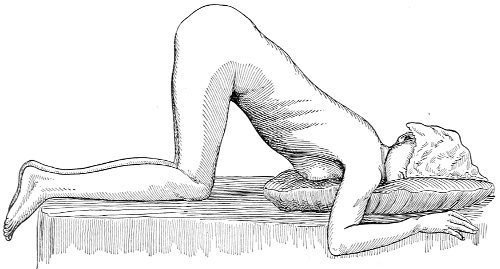

Percussion should then be performed with the woman upon her back, upon the right side, upon the left side, sitting up, and upon the hands and knees. An encysted fluid accumulation will give practically the same result in percussion in all positions, while free fluid will gravitate to the most dependent portion.

The Sims speculum enables us to make the most thorough inspection of the vagina, the vaginal vault, and the vaginal cervix. The Sims speculum is merely a hook or retractor for the perineum, and may be introduced with the woman in the dorsal position, the Sims position, or the genu-pectoral position. If the Sims speculum is introduced in the dorso-sacral position, it is necessary to hold forward the anterior vaginal wall in order to obtain a view of the cervix.

Fig. 10.—The Sims position.

The Sims position, which is also called the latero-abdominal position, is shown in Fig. 10. The woman is placed on the bed or table upon her left side. The side of the face is upon the pillow; the left arm is behind the back, so that the left breast rests upon the table. The thighs are flexed upon the abdomen at an angle of about 90° to the trunk. The right thigh is more flexed than the left, so that the right knee may touch the table above the left knee. The legs are flexed on the thighs. In this position there is a tendency for the intestines, following the force of gravity, to fall from the pelvis, 32 and for the uterus and other pelvic viscera to be drawn up. When the perineum is retracted with the blade of the Sims speculum, air will enter the vagina and the vaginal slit will become distended (Fig. 11). To facilitate inspection of the cervix it is usually necessary also to push forward the anterior abdominal wall by some kind of depressor, such as the one shown in Fig. 8.

The genu-pectoral position or the knee-chest position is shown in Fig. 12. The side of the face is upon the pillow; the breast is upon the table; the thighs are vertical. In 33 this position the intestines fall from the pelvis, and the other pelvic viscera are drawn upward by the force of gravity. If the anus is opened, air rushes in and distends the rectum. If the perineum is retracted, air enters and distends the vagina. If the urethra is opened, the bladder is likewise distended. The position is the most useful one for inspection of the rectum, vagina and vaginal cervix, and the bladder.